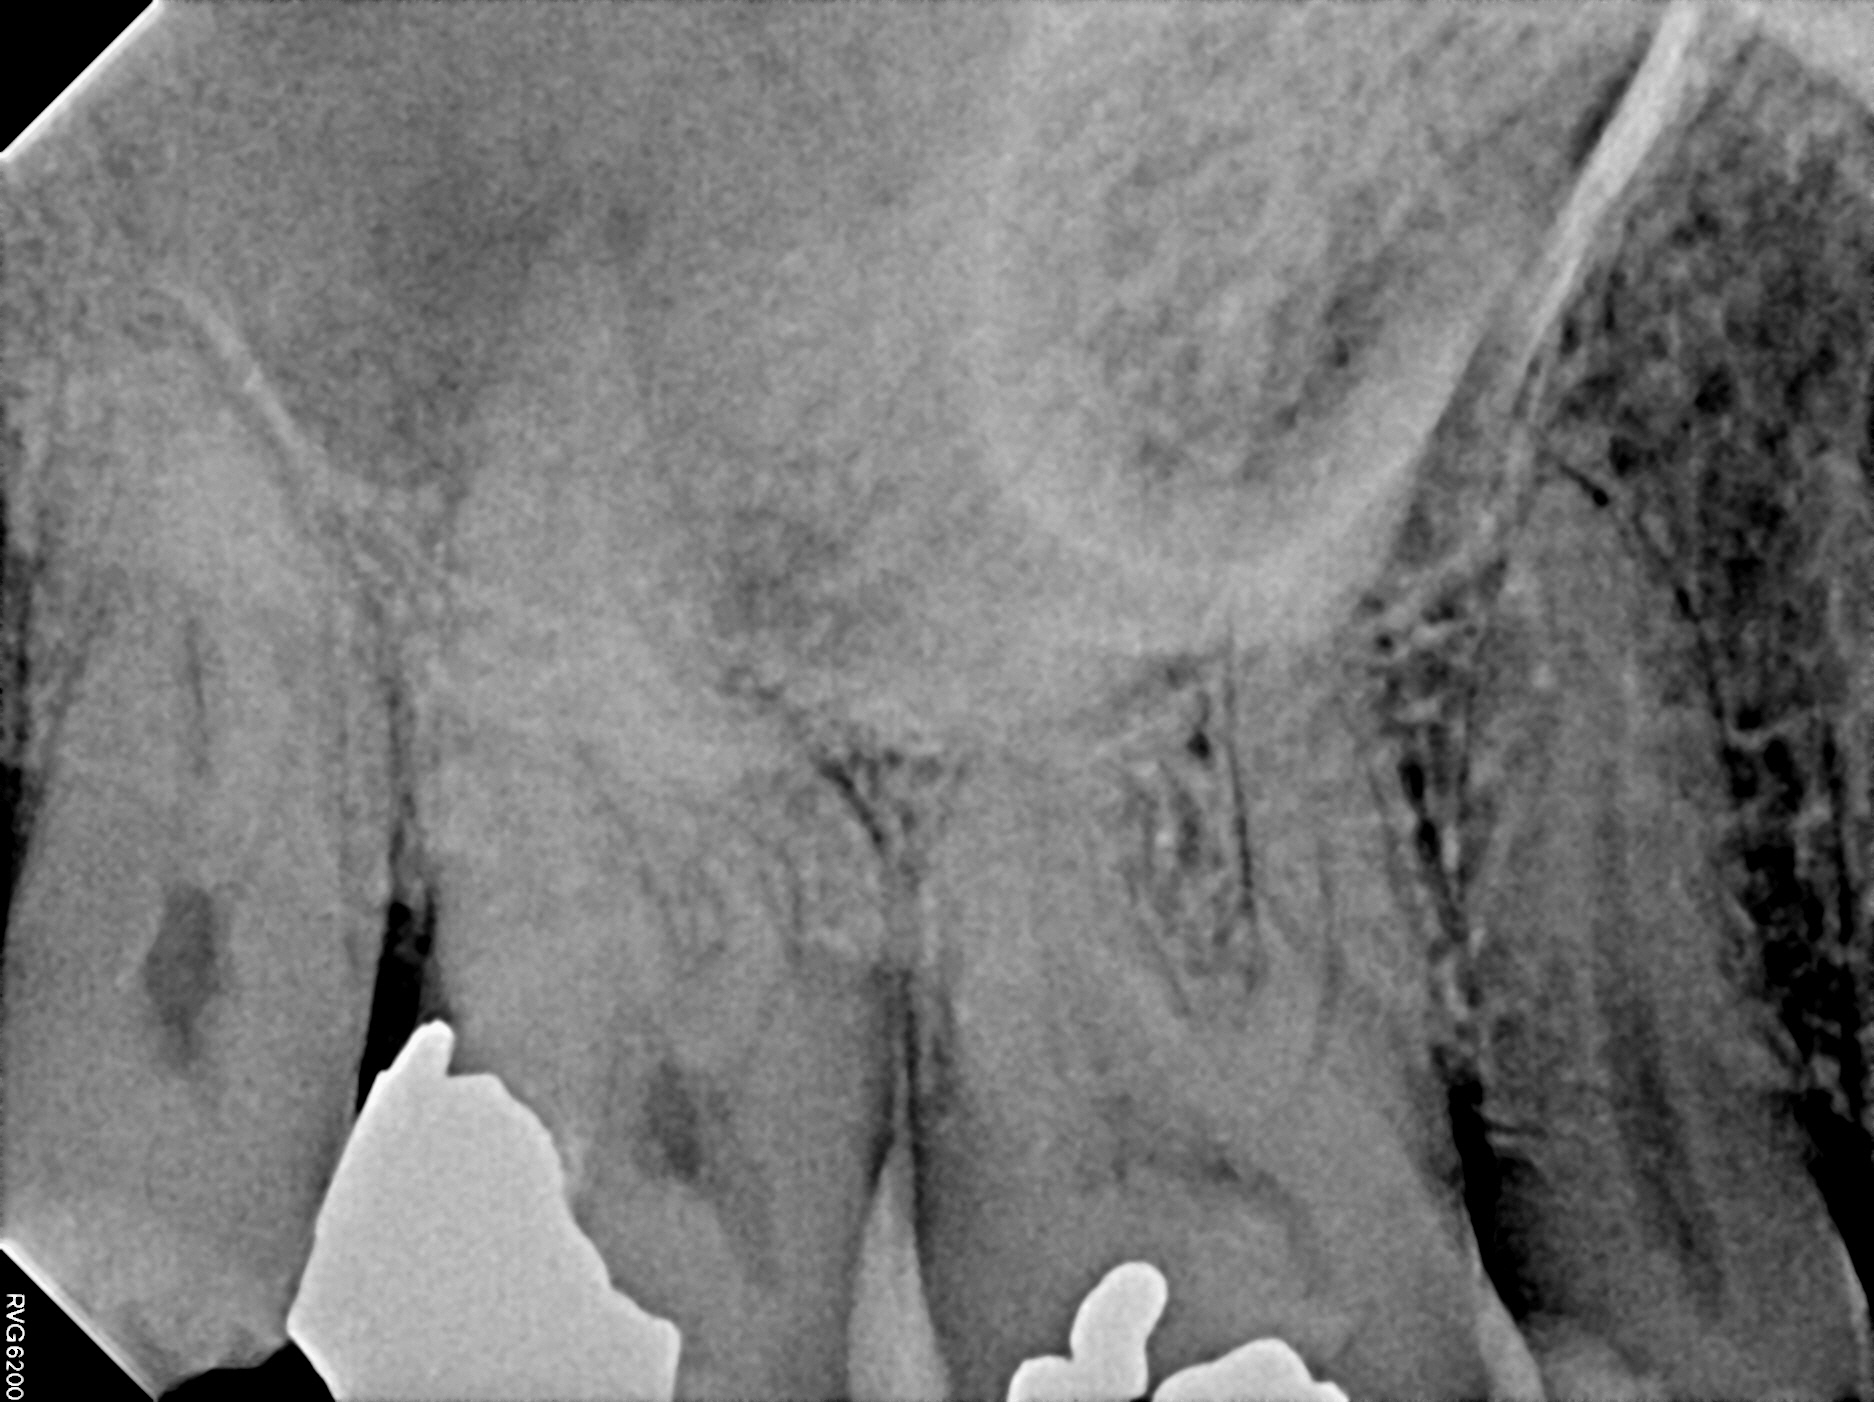

Case 13

The left image is prior to treatment. This tooth became infected due to a crack in the tooth. The darker areas above the root tips is the abscess. A crown was placed to protect the tooth from cracking further. The right image is 4 years later--we can see complete bone healing.